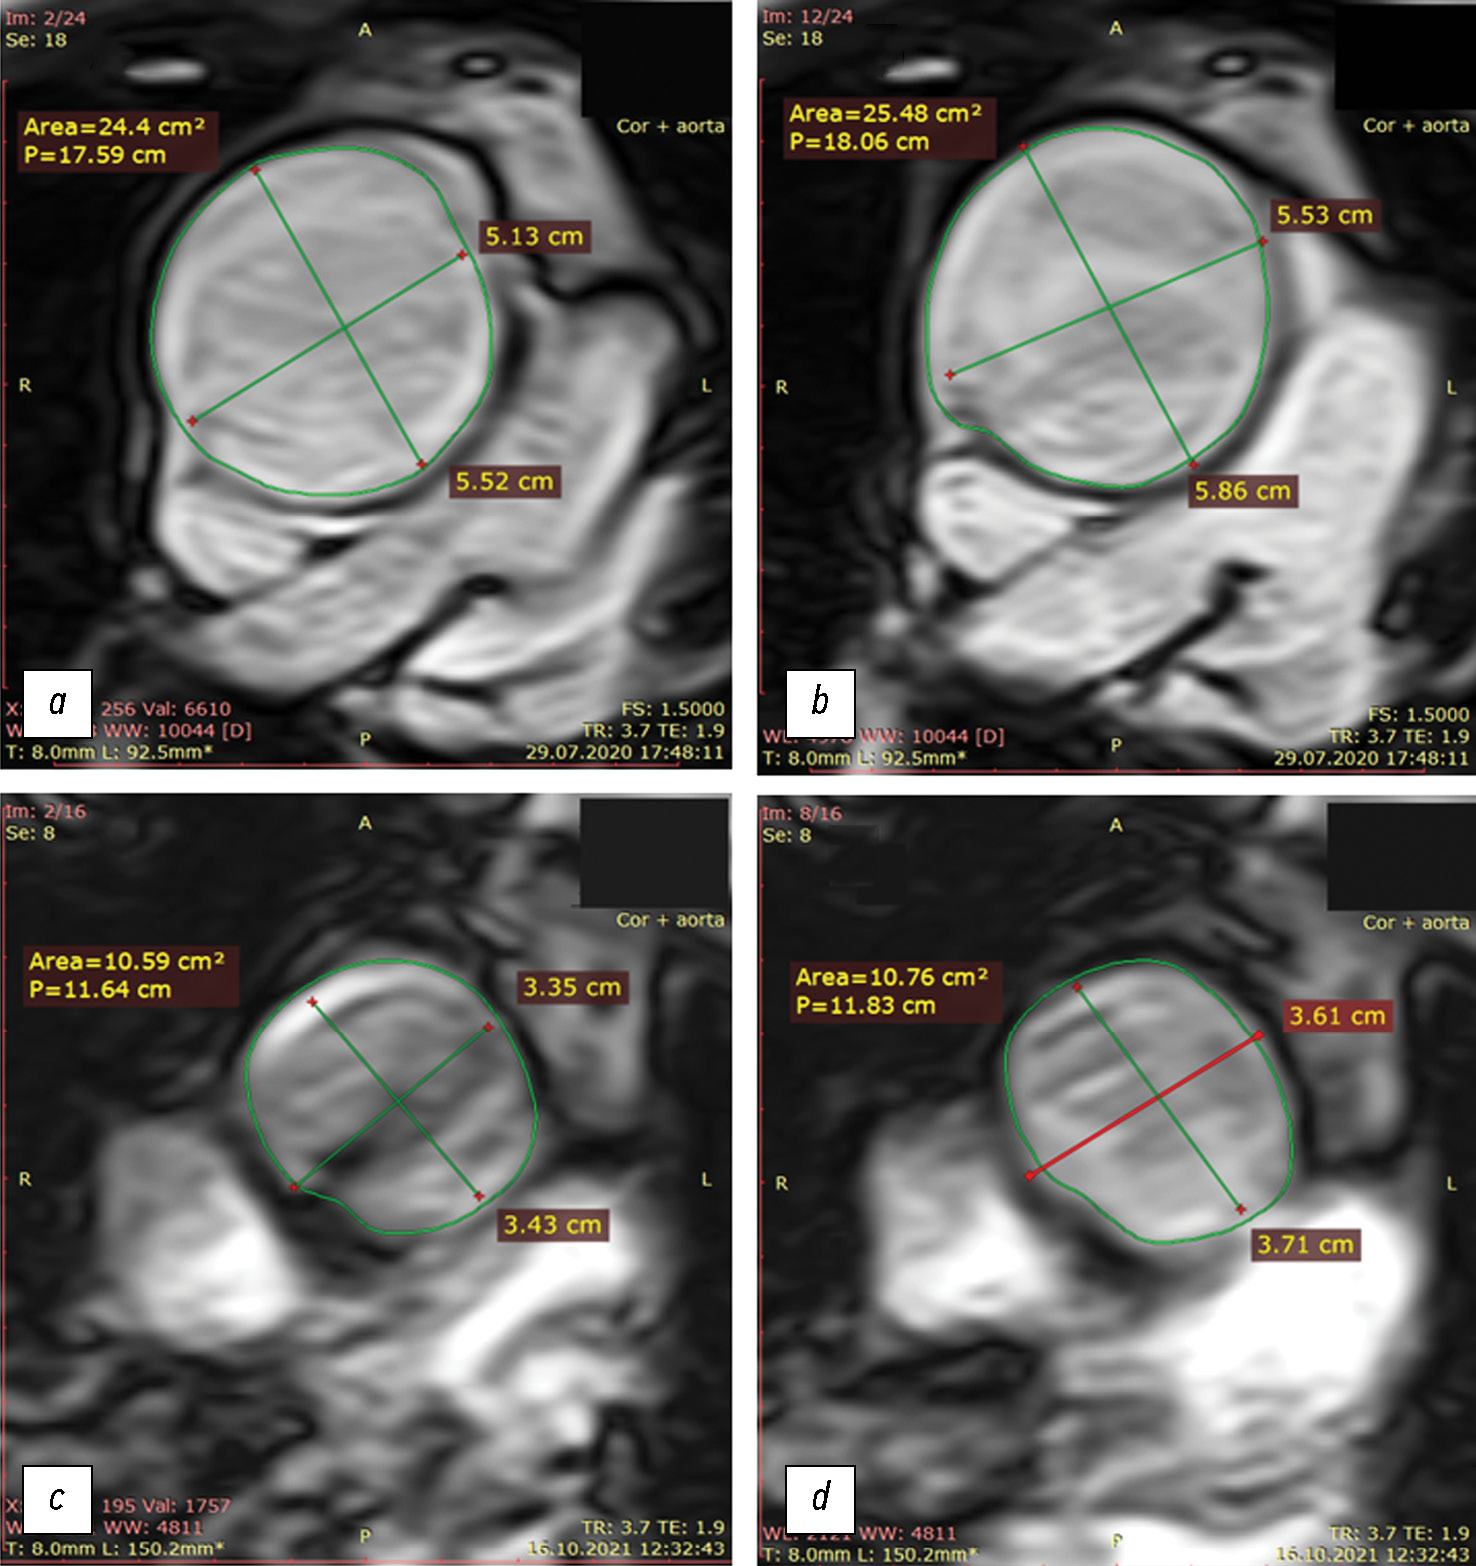

Fig. 3. Cross-sectional dimensions and areas of the ascending aorta during systole and diastole: top row: baseline (at admission; before replacement of the aorta that expanded due to aneurysm); bottom row: after replacement with a synthetic graft; (a, c) diastole; (b, d) systole. Of note is a considerable lumen narrowing after surgery, with a relatively small distensibility of the ascending aorta.

Aortic elasticity parameters improved dramatically following surgery; however, they still exceeded the normal value [8]. However, the systolic expansion volume of the ascending aorta (ΔVsyst) decreased significantly due to a decrease in the aortic diameter by 2 cm.

The postoperative Young’s modulus for the aortic wall (specifically, for the ascending aortic graft) decreased, whereas the elasticity increased. However, generally, the systolic expansion volume of the aorta decreased to approximately 5 mL (Table 2), which is insufficient for adequate coronary blood supply [8]. The physical dimensions of the graft corresponded to those specified in the documents. Thus, even in the absence of significant coronary stenoses and with an ideal surgical technique of ascending aortic replacement, insufficient distensibility of the aortic wall became a critical factor, limiting exercise tolerance after surgery and contributing to left ventricular failure, although without acute myocardial infarction.